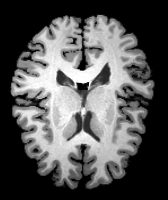

Image Manual Seg DA-1 Mono-21 DA-21 Mono-65 Refer to caption Refer to caption Refer to caption Refer to caption Refer to caption Refer to caption

Figure 2:  Examples of knee MRI registration (top) and brain MRI segmentation (bottom) results. Top: The first two columns are the moving image/segmentation and the target image/segmentation followed by the warped moving images (with deformation grids)/segmentations by different models. Bottom left to right: original image, manual segmentation, and predictions of various models. Mono-i𝑖i and DA-i𝑖i represent the mono- and DA models with i𝑖i manual segmentations respectively.

Results: All trained networks are evaluated using Dice overlap scores between predictions and the manual segmentations for the segmentation network, or between the warped moving segmentations and the target segmentations for the registration network. Tabs. 1 and 2 show results for the knee and brain MRI experiments respectively in Dice scores (%). Fig. 2 shows examples of knee MRI registrations and brain MRI segmentations.

Qualitative results: DA achieves more anatomically consistent registrations than the mono-networks on the knee (Fig. 2) and Brain MRI samples (see supplementary material).

Image Manual Seg DA-1 Mono-5 DA-5 Mono-200 Refer to caption Refer to caption Refer to caption Refer to caption Refer to caption Refer to caption

Figure 4: Examples of brain MRI registration (top) and knee MRI segmentation (bottom) results. Top: The first two columns are the moving image/segmentation and the target image/segmentation followed by the warped moving images/segmentations by different models. Bottom left to right: original image, manual segmentation, and predictions of various models. Mono-i𝑖i and DA-i𝑖i represent the mono- and DA models trained with i𝑖i manual segmentations respectively.